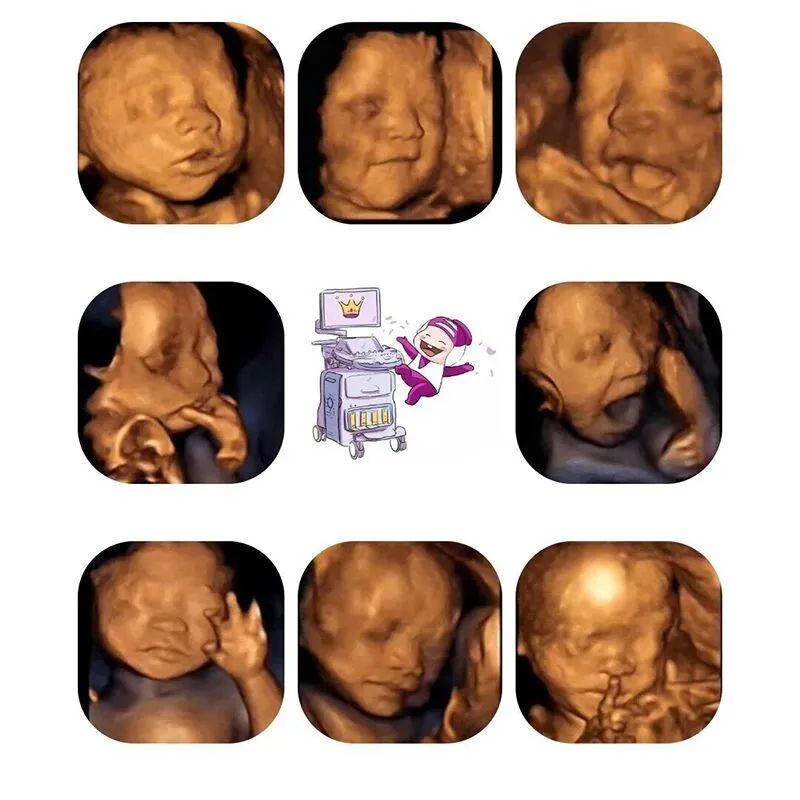

在艾玛,整个检查过程,胎儿的四维画面可通过显示屏幕同步直播,孕妈妈和家属可同时观看,让家人起见证生命初的感动。

成像清晰且是动态影像

加上这个时期母体羊水充足

宝宝在妈妈肚子里活动空间大

所以宝妈们还可通过屏幕

提前看到宝宝的模样

如果宝宝在宝妈做超声影像(四维彩超)那会儿正面对你,并且五官周围羊水很充足,那时成像就会较为清晰。

但是如果宝宝正好脸背着你,或者脸部周围羊水不多,宝宝因皮肤呈皱褶状态,还有层胎脂保护着宝宝,超声波的折射不平,也会影响图片的清晰度。有些宝宝的头部位置比较低,头在骨盆内,宝妈骨盆的骨骼会干扰我们的仪器,导致宝宝面部图像模糊。

还有种情况,如果宝宝将面部靠近子宫壁,或者低头将身体蜷缩起来,或者宝宝的背部朝外靠近宝妈的腹部(也就是宝宝与宝妈面对面的),医生将采集不清甚至无法采集到宝宝的面部图像。